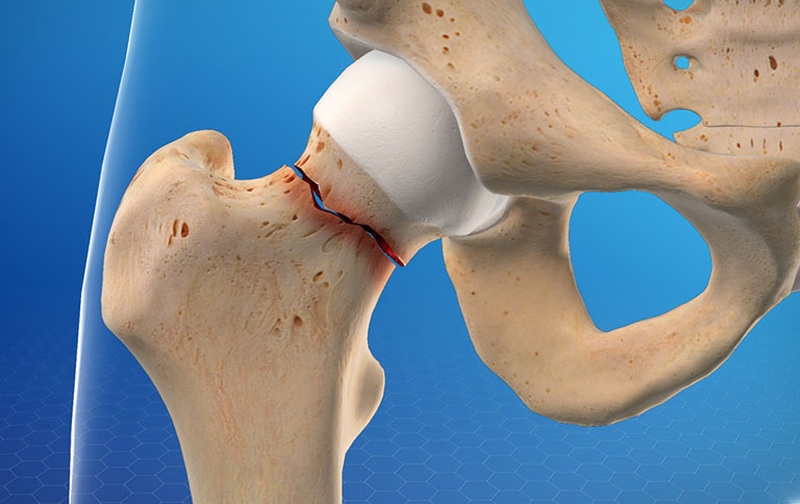

Thời gian liền xương gãy nhanh hay chậm phụ thuộc vào mức độ tổn thương cũng như tuổi tác của người bệnh. Thời gian này nhanh hơn đối với những người trẻ.

Bên cạnh đó quá trình này còn phụ thuộc vào tình trạng bệnh nền mãn tính đi kèm của người bệnh như: Tiểu đường, viêm phổi, loãng xương,... Những đối tượng mắc bệnh lý này có thể khiến cho thời gian liền xương lâu hơn,... đồng thời hạn chế khả năng vận động sau hồi phục. Xương liền thẳng hay cong cũng phụ thuộc trực tiếp vào việc vùng bị gãy có được cố định tốt hay không.

Thời gian liền xương khác nhau tùy từng trường hợp

Cố định chính là một phần bắt buộc của quá trình điều trị. Bởi bất kỳ chuyển động nào tác động lên các mảnh xương gãy cũng có thể đều làm chậm quá trình chữa lành xương ban đầu. Tùy thuộc vào chấn thương cũng như loại hình điều trị, bác sĩ có thể chỉ định cho bạn bó bột hoặc là sử dụng nẹp để cố định chân gãy.